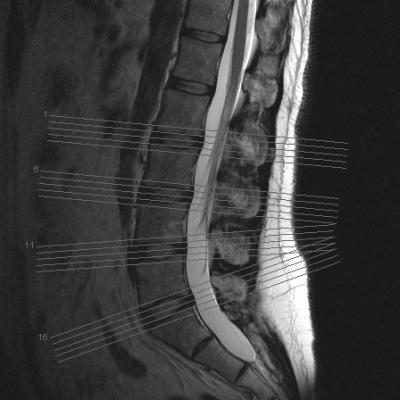

war wegen hodenschmerzen beim urologen, dieser schaute sich u.a. meinen rücken an, schickte mich dann zum orthopäden und dort wurde dann u.a. ein mrt gemacht. habe noch keinen weiteren termin zur besprechung bekommen, aber die bilder schon mal mitbekommen.

diese sind nun im anhang und mich würde interessieren ob ihr hier vielleicht schon was dazu sagen könnt.

mich würde aufgrund der bilder nur hier mal interessieren ob das eine skoliose ist.

- forum_photo.jpg (17.85 KiB) 2599 mal betrachtet

Eine Skoliose (seitliche Verbiegung der WS) ist für mich nicht zu erkennen. Wenn das zweite Bild eine seitliche Aufnahme der LWS ist, sieht man dort eine deutliche Lordose.

Ich erkenne auch keine Skoliose, ABER MRT´s werden ja im Liegen aufgenommen und da wird der Rücken ganz anders belastet, so dass liegende Aufnahmen zur Diagnostik von Skoliose oder auch Kyphose/Lordose nicht geeignet sind. Für Bandscheibenschäden und Strukturen etc. ist ein MRT sinnvoll, aber nicht zur Bestimmung einer Skoliose. Dazu benötigt man Röntgenaufnahmen im Stehen von vorne und von der Seite (Ganzaufnahmen!!). Wie kommst du denn auf Skoliose, hatte man bei dir den Verdacht??